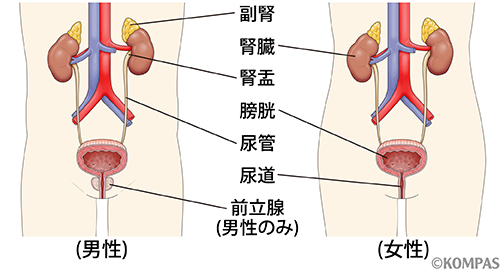

究める鏡視下膀胱全摘術・尿路変向術 Level up LRC, RARC | 三木。メジカルビュー社|泌尿器科|究める鏡視下膀胱全摘術・尿路変向。ロボット支援膀胱全摘除術(RARC) | 岩手医科大学 泌尿器科学講座。★3月精米★ 令和6年産 福井県産 いちほまれ 5kg 白米 精米。膀胱がん【泌尿器科疾患について】 - 東京慈恵会医科大学 泌尿器科。膀胱がん|KOMPAS。手術手技(膀胱全摘除術) | 領域情報 | アステラスメディカルネット。膀胱がん|KOMPAS。周術期の負担を軽減し早期社会復帰を!「ロボット支援腹腔鏡下。腎盂尿管移行部狭窄症に対するロボット支援腹腔鏡下腎盂形成術。朝倉書店『内科学』(第12版)デジタル付録。腹腔鏡下尿膜管摘出術及び左腎摘出術 - Olympus Professional。ロボット手術の定番!新品、未使用です。間違って2冊買ってしまったので、ページを開いてもいないため、本屋さんの「売上スリップ」も付いたままの全くの新品です。膀胱がんの外科治療について | 小野薬品 がん情報 一般向け。